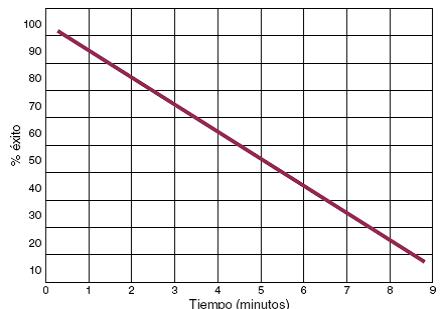

El tratamiento del paro cardiaco súbito secundario a FV o TV es la desfibrilación ventricular31, y cuanto más temprano se realice, mayor será la posibilidad de revertir a ritmo sinusal (Fig. 2). Al primer minuto, el éxito de la desfibrilación ventricular es superior al 90%, y desciende 7-10% por minuto sin reanimación cardiopulmonar (RCP); con RCP la probabilidad de revertir a ritmo sinusal desciende, de un 3-4% por minuto32. La RCP prolonga la ventana de tiempo para poder realizar desfibrilación exitosa33. Se deberá realizar la cadena básica de supervivencia ante un paciente en paro cardiaco. Dicha cadena implica la detección temprana del paciente y activación del sistema de urgencia médica, RCP temprana, desfibrilación temprana, cuidados avanzados tempranos y cuidados tempranos posreanimación. Al realizar todos los eslabones de la cadena de supervivencia dentro de los primeros 5 min del colapso, se mejoran de forma significativa las tasas de supervivencia de estos pacientes31-34 (Fig. 3). La colocación de desfibriladores externos automáticos en sitios públicos junto con la realización de maniobras básicas de RCP por el observador de una víctima de paro cardiaco súbito ha demostrado que mejora significativamente la supervivencia, por lo que se recomienda ampliamente la colocación de desfibriladores externos automáticos y el entrenamiento al público en maniobras básicas de RCP en escuelas, aeropuertos, gimnasios, empresas y lugares estratégicos de la comunidad con alta densidad poblacional35. El desfibrilador automático implantable (DAI) es un equipo con alta posibilidad de revertir a ritmo sinusal un episodio de TV o FV ya que puede desfibrilar en menos de 15 seg una de estas arritmias36-39. La FV produce una contracción irregular y caótica del miocardio ventricular, con la consecuente incapacidad del corazón para mantener el flujo sanguíneo corporal; de no ser revertida a ritmo sinusal, pasará a asistolia y posteriormente causará la muerte del paciente32,36. En la Figura 4 se muestran ejemplos de FV, ritmo agónico y asistolia.

Figura 2 Relación entre el tiempo transcurrido y la posibilidad de revertir a ritmo sinusal con desfibrilación, en casos sin reanimación cardiopulmonar. Adaptada de: Cummins58.